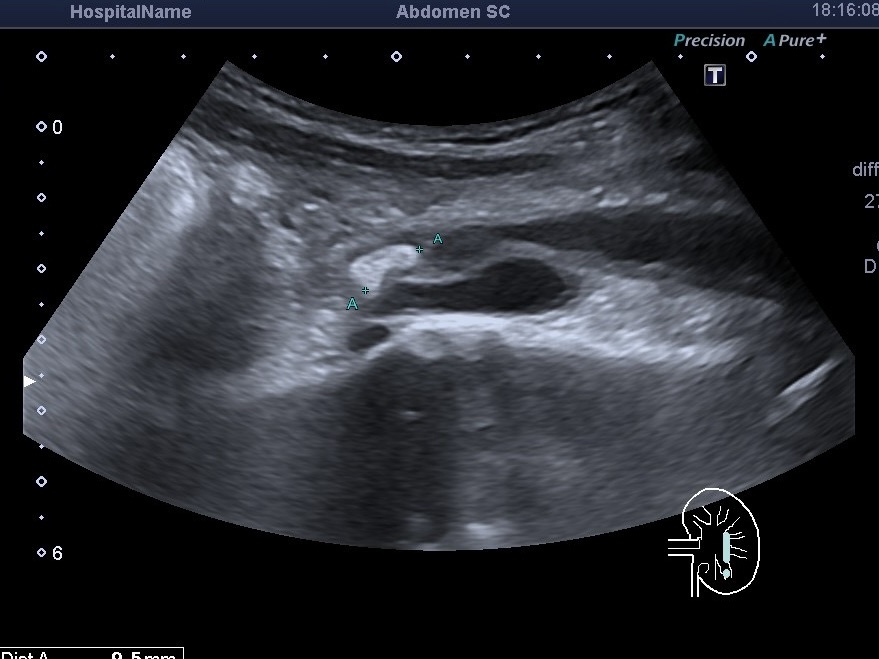

1. Гидронефроз левой почки: значительное расширение лоханки, чашечек и мочеточника.

2. Конкремент в почке: в одной из чашек визуализировался камень около 6 мм.

3. Отсутствие выброса мочи: при осмотре мочевого пузыря было заметно, что выброс из левого мочеточника не происходит (работал только правый). Это означало наличие «блока» в мочеточнике.

Средняя часть мочеточника обычно плохо видна на УЗИ, и в таких случаях требуется КТ. Однако, благодаря телосложению пациента, мне удалось обнаружить камень длиной 10-12 мм в средней части мочеточника. Именно он блокировал отток мочи и вызывал боли.